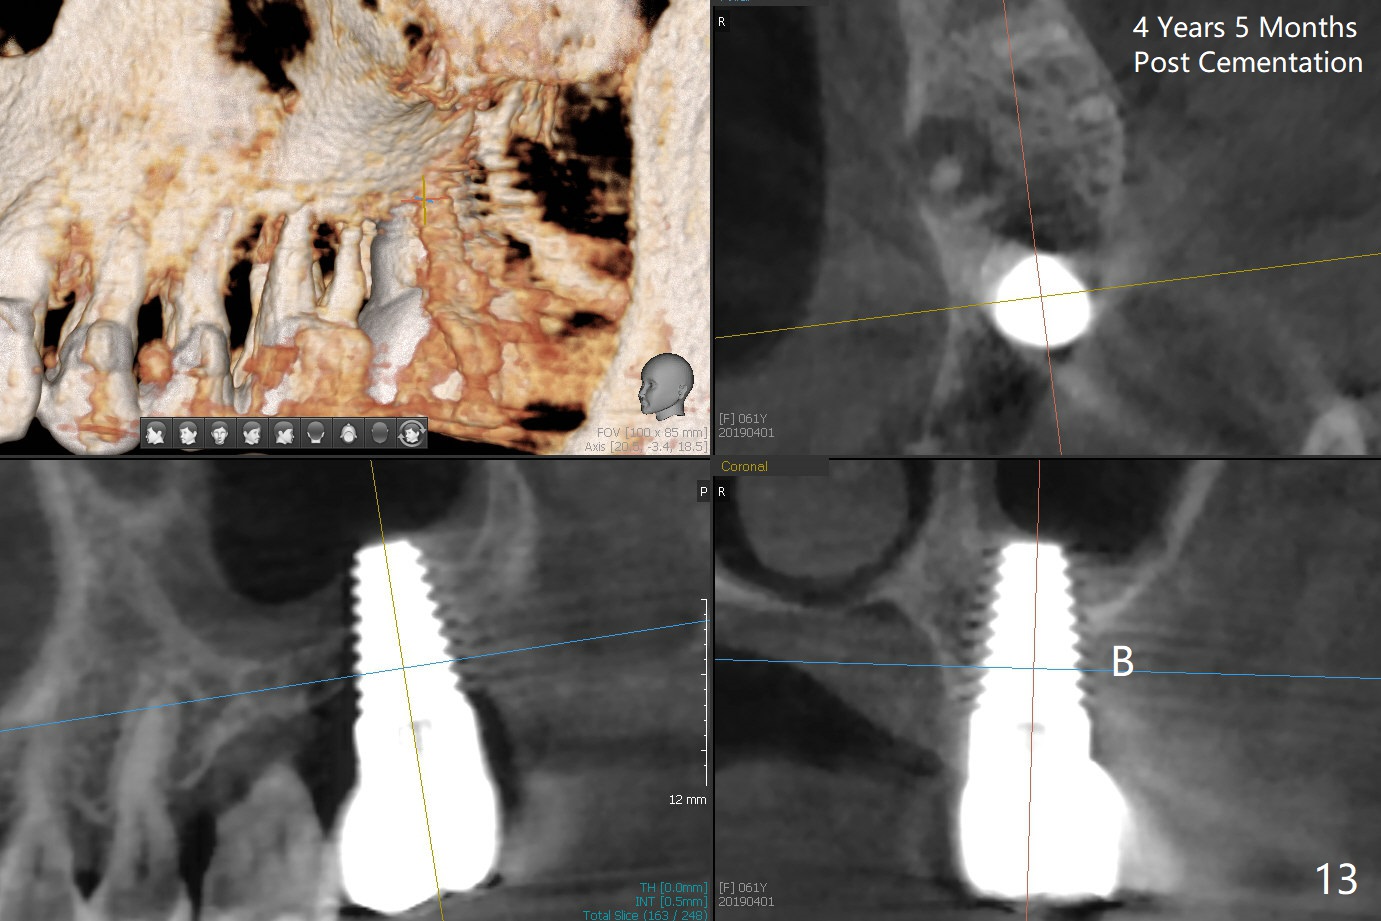

Model study shows that the implant is placed distally (Fig.9,11) in addition to buccal implant exposure (Fig.10 arrowheads). Postop, the patient complains of upper left discomfort, which is more likely associated with furcal infection of the tooth #14. The symptom disappears after use of water pik. Panoramic X-ray is taken 6 months post cementation (Fig.12).